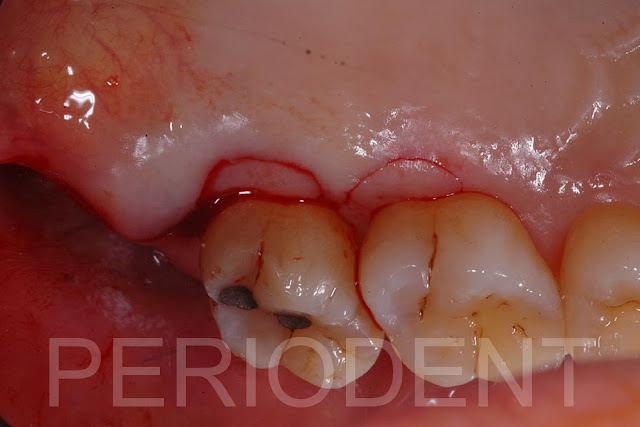

陳柏堅醫師發表上顎Distal Wedge手術之病例二